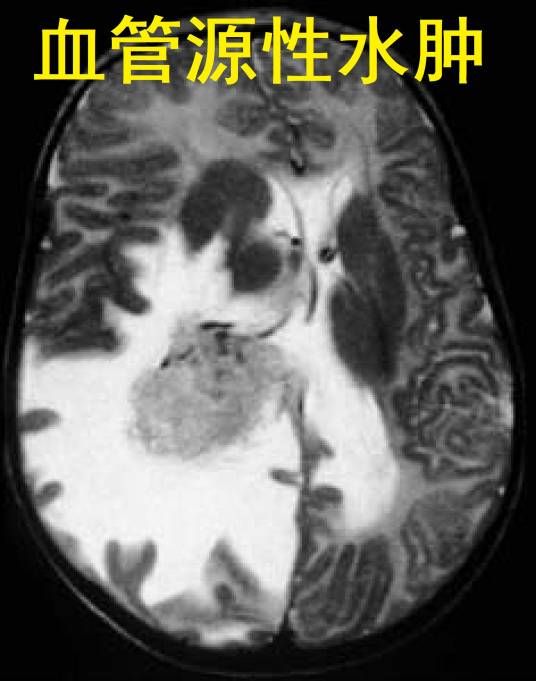

CT或MRI:CT或MRI扫描时直接提示脑水肿的最可靠诊断方法,CT图像所显示的征象,在病灶周围或白质区域,不同范围的低密度区,MRI在T1或T2加权像上,水肿区为高信号,较之CT扫描结果更确切。